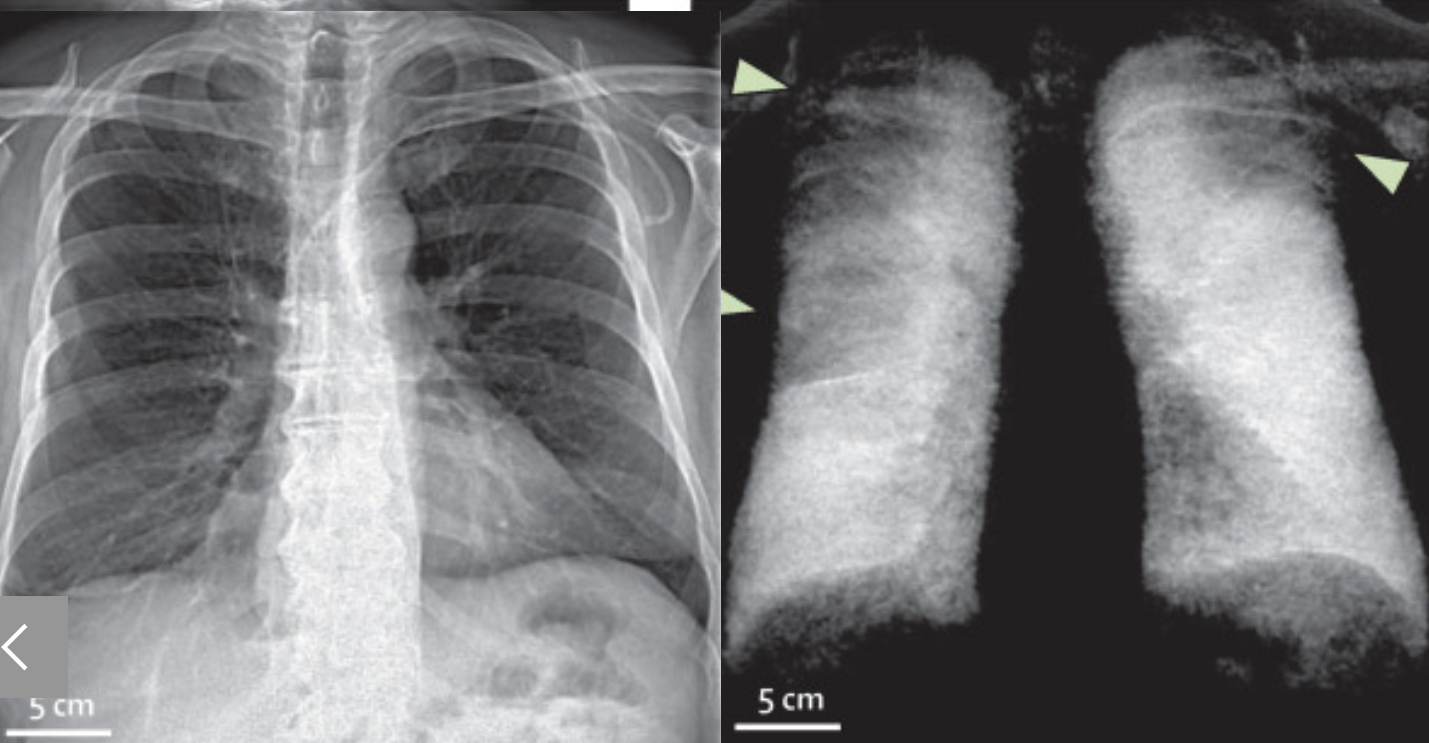

Les innovations technologiques permettent aussi de prévoir nouvelles applications et d’affiner la pratique clinique existante. La TDM à comptage photonique, qui utilise des semi-conducteurs convertissant directement les photons X en impulsions électroniques, est l'avancée majeure la plus récente puisqu’elle augmente la résolution spatiale et réduit le bruit et la dose de rayonnement. Il en résulte une amélioration de la visualisation des anomalies interstitielles et des nodules pulmonaires et la possibilité de reconstruire des images rétrospectivement à une variété d'énergies de photons. Parmi les évolutions technologiques, citons l’IRM, notamment le ciné-IRM dynamique pour l'évaluation de la trachéomalacie ou l’IRM au xénon hyperpolarisé pour une cartographie fonctionnelle et une quantification de la perfusion pulmonaire, de la ventilation et des échanges gazeux importants pour évaluer les symptômes de l'état post-COVID-19 (COVID long). Citons également la radiographie thoracique à fond noir, qui peut jouer un rôle dans l'analyse fonctionnelle des maladies pulmonaires et la détection des anomalies de la ventilation.